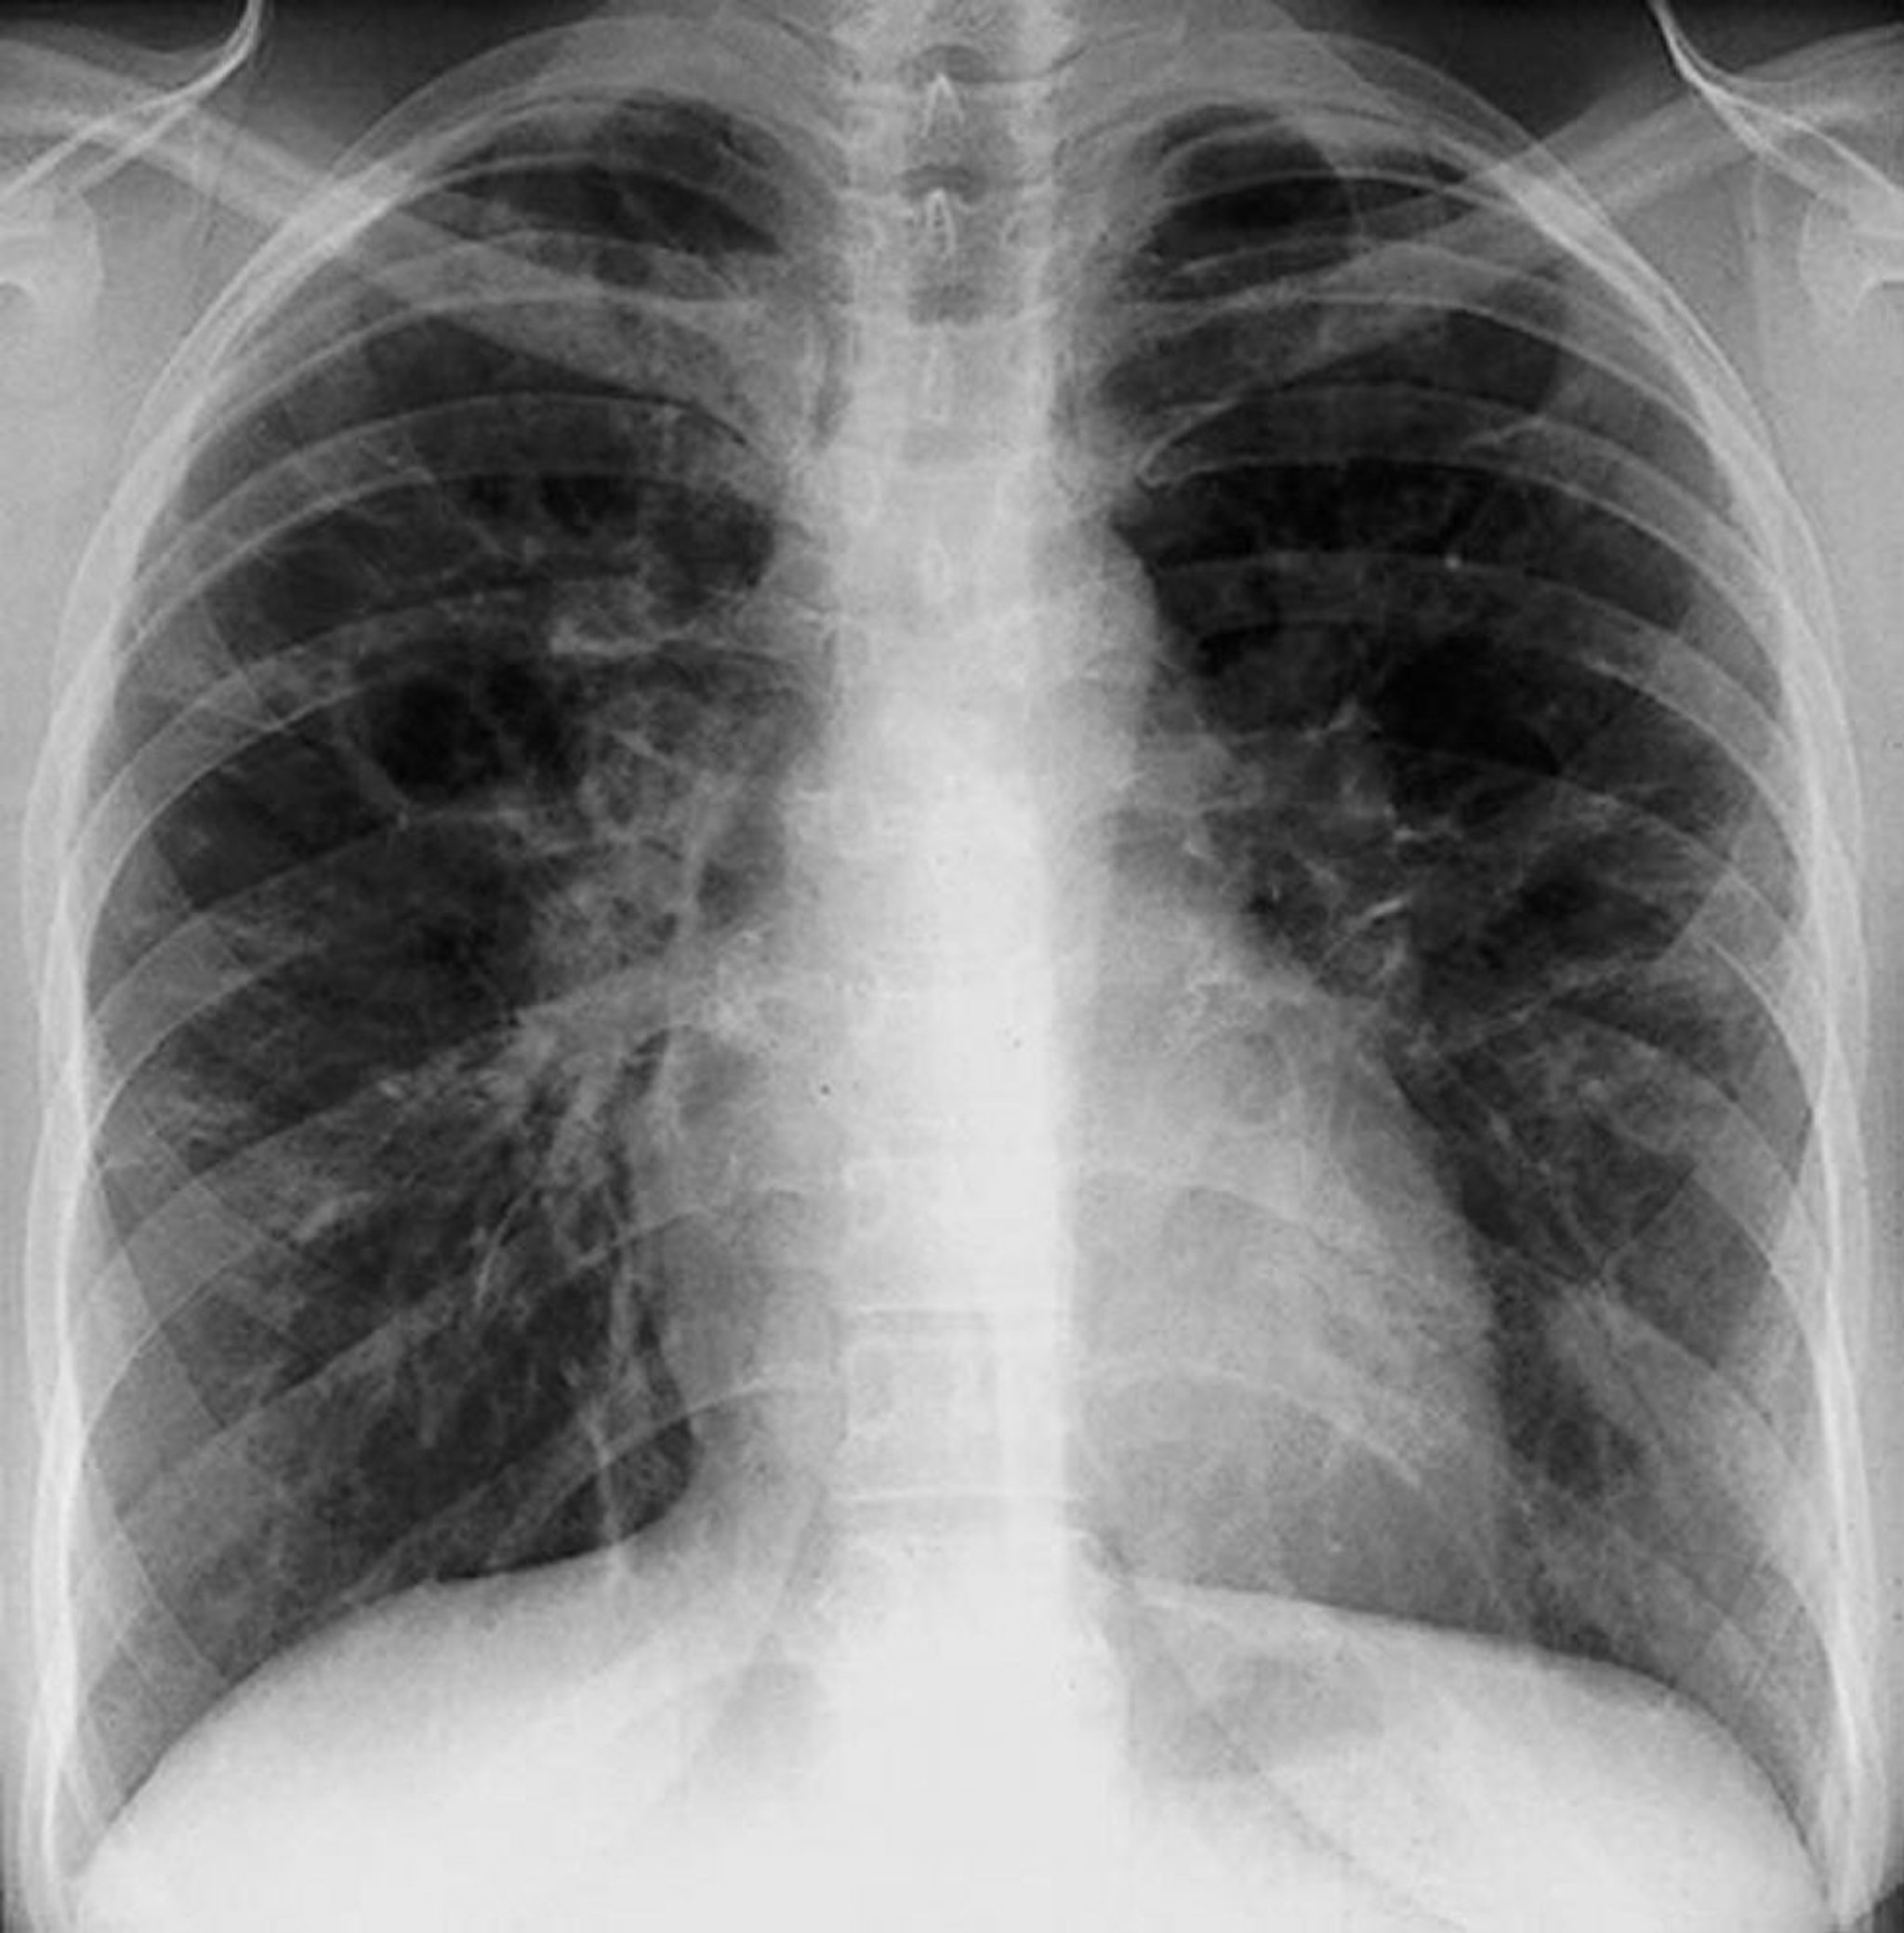

Sarcoidosis (Stage III)

Diffuse interstitial opacities without hilar adenopathy in stage III sarcoidosis.

By permission of the publisher. From Tanoue L, Elias J. In Bone's Atlas of Pulmonary and Critical Care Medicine. Edited by J Crapo. Philadelphia, Current Medicine, 2005.